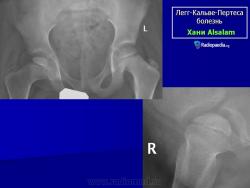

Остеохондропатия головки бедренной кости

(болезнь Легга-Кальве-Пертеса)

Рентгенологическое обследование помогает в постановке диагноза. Для сравнительного анализа производят рентгеновские снимки обоих тазобедренных суставов, а также рентгенограмму в положении Лауэнштейна. Наиболее полную информацию о локализации и распространенности патологических изменений в головке бедра дает компьютерная и ядерно-магнитно-резонансная томография тазобедренных суставов. В ранней диагностике заболевания высокоэффективно радиоизотопное исследование (сцинтиграфия).

Во II стадии (импрессионного перелома) головка бедренной кости утрачивает характерную трабекулярную структуру, шейка бедра становится более остеопоротичной. Суставная щель отчетливо расширяется по сравнению со здоровым тазобедренным суставом. Эпифиз головки уплотняется, склерозируется и деформируется (вследствие сохраняющейся нагрузки).

В III стадии (фрагментации эпифиза) суставная щель по-прежнему расширена, головка сплющена и как бы разделена на отдельные глыбки или неправильной формы мелкоочаговые фрагменты. Обычно определяется от 2 до 5 таких фрагментов, а иногда и больше. Вертлужная впадина уплощается.